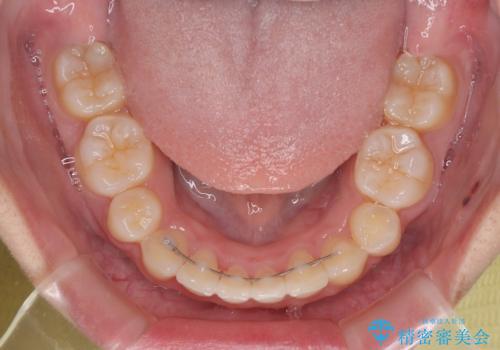

上下正中位置を改善するため、左下はイレギュラーに第二小臼歯を抜歯しました。そのため治療期間の長期化が予想されましたが、2年半ほどで期待通りの歯列に仕上げることができました。

- 2年7ヶ月

- 30回以上